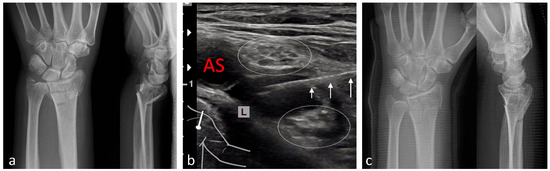

| Radius | 111 | Brachial plexus block (infraclavicular)/10–20 |

| Wrist | 1 | Brachial plexus block (infraclavicular)/15–20 |